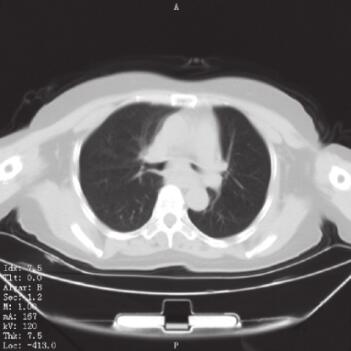

入院后检查:生命体征平稳,慢性病容,呼吸急促,口唇及甲床不发绀。上肺部可闻及双相哮鸣音,以吸气相为主,心率90次/分,律齐,各瓣膜听诊区未闻及杂音,肝脏、脾脏在肋缘下未能触及,剑突下无压痛,双下肢不水肿。血常规:WBC 7.66×109/L,N% 75.0%,HGB 135g/L,PLT 290×109/L。红细胞沉降率23mm/h。肝肾功能、生化未见异常。血气分析提示:pH 7.42,PaO2 80mmHg(1mmHg=0.133kPa),PaCO2 38mmHg。凝血指标及D-Dimer定量检测均在正常范围。入院后复查肺部CT(图1)。

图1 入院后肺部CT表现

A.隆突下肺窗显示隆突稍增宽;B.肺窗显示左肺舌叶炎性改变;C.隆突下纵隔窗显示隆突稍增宽

CT报告为左肺舌叶炎性改变,未见明确的占位性病变,考虑患者无咳痰,体温正常,血常规正常,无临床感染依据,未给予抗感染治疗,与家属进行沟通后决定完善电子支气管镜检查并在左主支气管新生物处取得病理组织。

5. 气管镜检查确诊后再次复习肺部CT表现,发现隆突较正常水平稍有增宽。本患者经过气管镜检查最终得到了确诊,但是家属拒绝进一步诊治使我们感到遗憾。